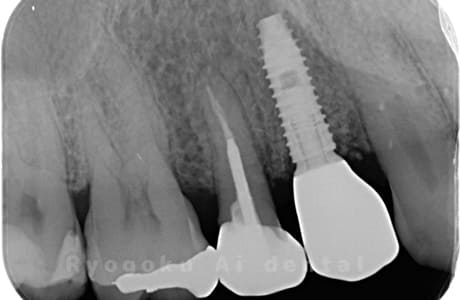

Case12

-

- 原因

- 右上5番歯根破折

- 治療内容

- インプラント治療

- 治療費用

- 約600,000円

左上に違和感があるとのことでご来院された患者様です。歯が割れているため、抜歯と診断し、即時でインプラント埋入を行いました。大変ご満足して頂けました。

<リスク・副作用>

治療後、痛みや違和感、出血、腫れなどが出る事があります。喫煙者、糖尿病などの方の場合、歯が生着しない場合があります。